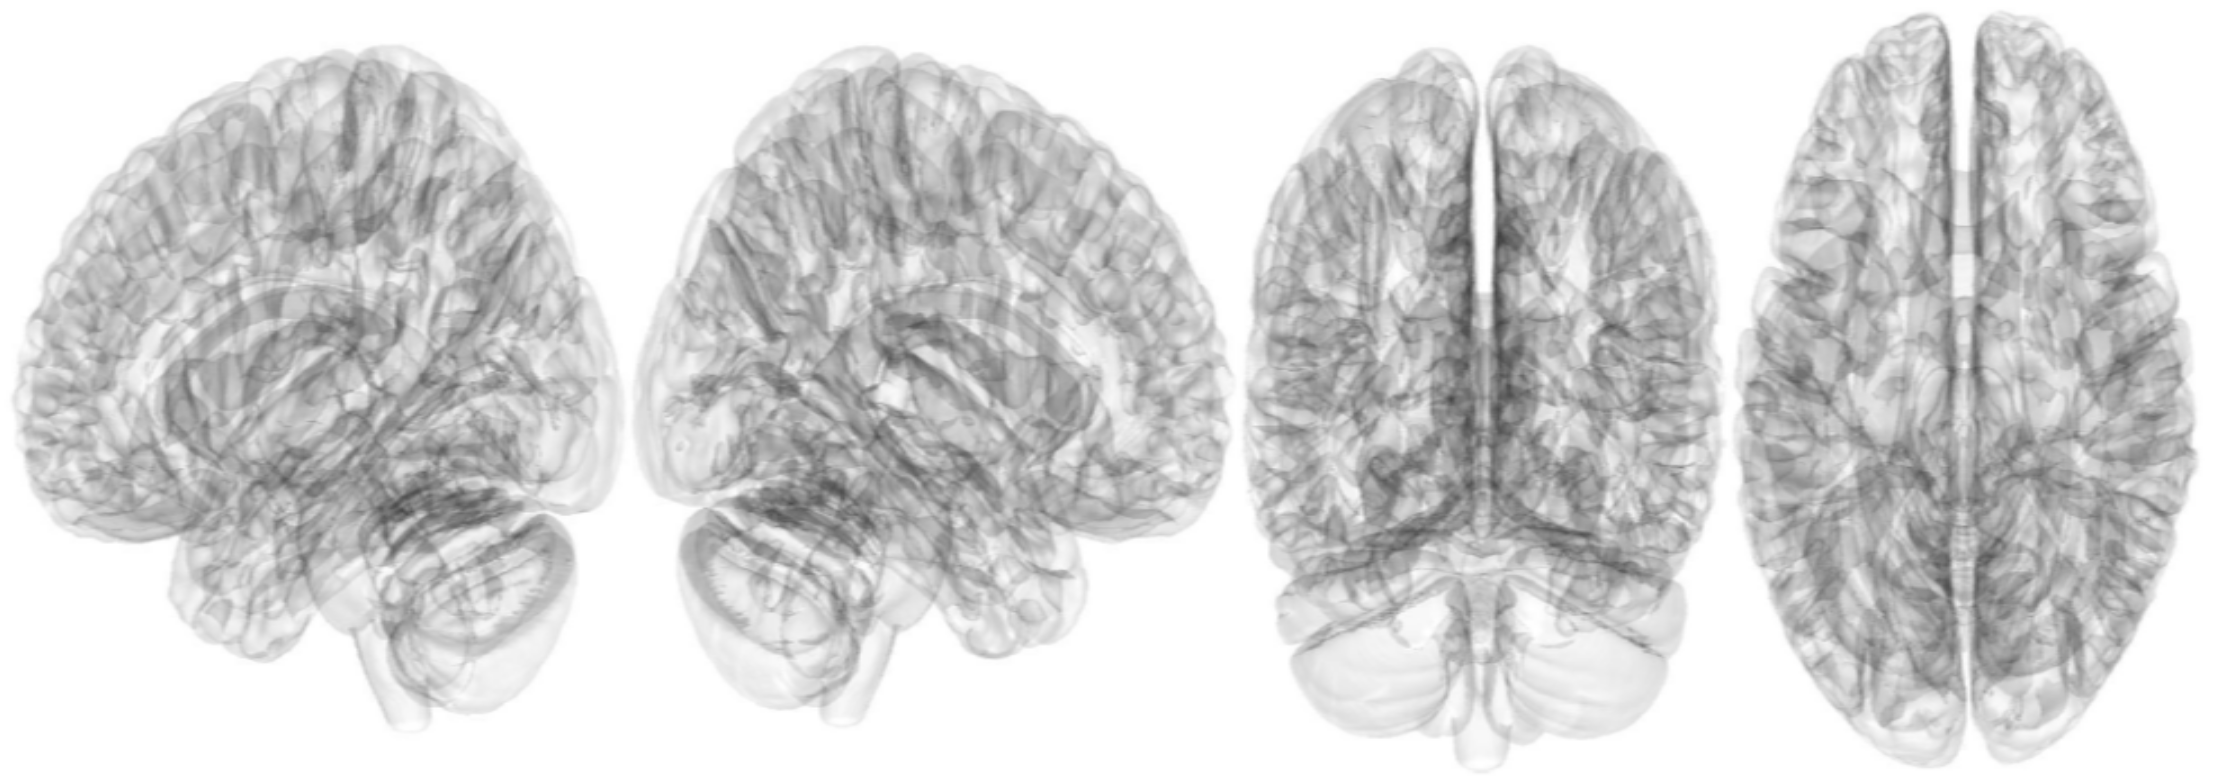

2.3. Connectometry Analysis with Statistical Analysis